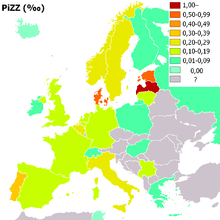

People of northern European, Iberian ancestry are at the highest risk for A1AD. Four percent carry the PiZ allele; between 1 in 625 and 1 in 2000 are homozygous.

Another study detected a frequency of 1 in 1550 individuals and a gene frequency of 0.026. The highest prevalence of the PiZZ variant was recorded in the northern and western European countries with mean gene frequency of 0.0140.[11]